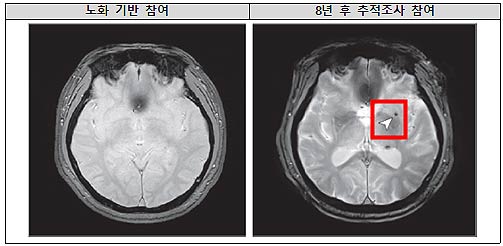

8년 후 뇌 미세출혈이 발생한 뇌영상 이미지

연구팀은 노화 심층조사사업 참여자 중 중장년층 1,441명을 8년 간 추적하여 수면무호흡의 중증도가 뇌 미세출혈 발생에 미치는 영향을 분석했다.

연구 결과, 중등도 이상의 폐쇄성 수면무호흡증을 가진 사람은 수면무호흡증이 없는 사람에 비해 뇌 미세출혈이 발생할 위험이 약 2배 증가하는 것으로 나타났다. 반면, 경증 수면무호흡증에서는 위험 증가가 관찰되지 않았다.